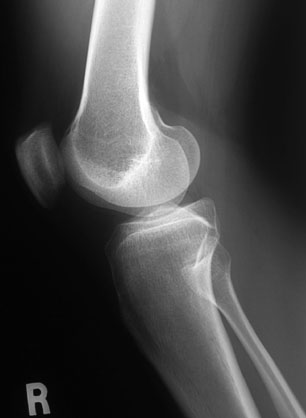

Knee -- Lateral View, Unlabelled

Click on a structure to learn its name

Show Me a Labelled Version